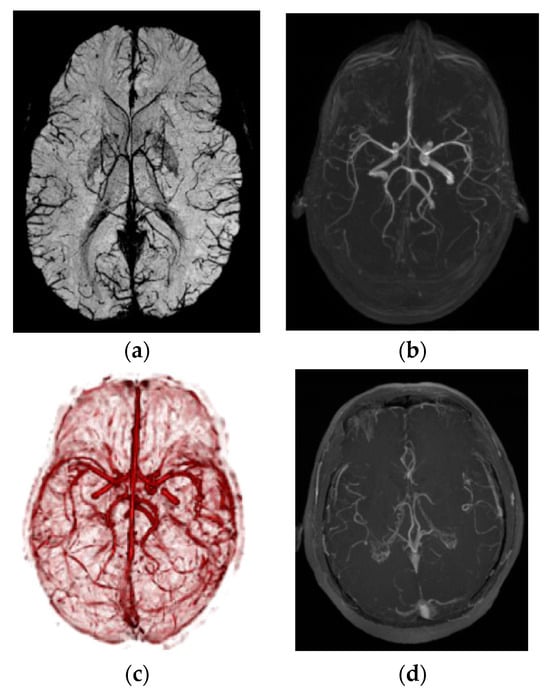

Path planning is a primary workflow step for all image-guided keyhole neurosurgeries. Path planning for percutaneous interventions involves finding a safe and feasible/optimal path for needle insertion by avoiding obstacles within the body to reach the targets defined by a clinician or a computer-based algorithm. Obstacles or critical structures refer to any tissue that cannot be damaged or punctured by the needle such as bone, nerves, or arteries. Figure 2 shows different critical structures segmented on an MR image dataset. A target can refer to a planned implant location of a seed, a point within a tumor for biopsy and ablation, or the appropriate distal location of an electrode in the brain for DBS.

Figure 2.

Path-planning example showing trajectory and critical structures. Blue: cerebrospinal tract (CST); pink: hypometabolism PET; deep pink: SPECT; cyan-red: blood vessels; green arrow: historical trajectory [].